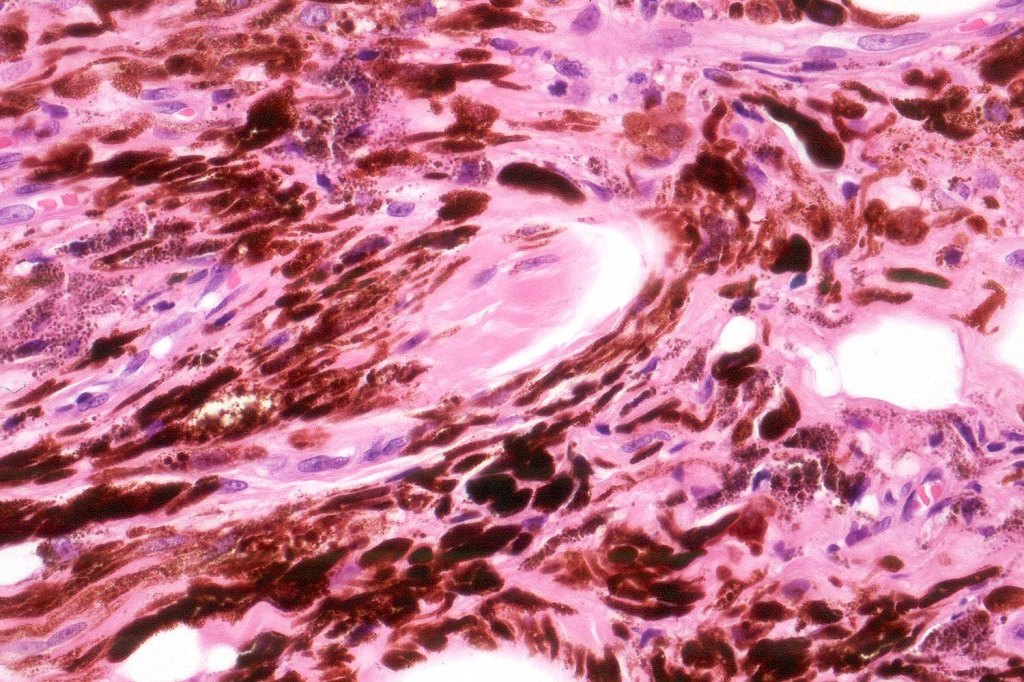

Histologically, it is characterized by a dense population of spindled, dendritic melnanocytes & melanophages with variable fibrosis. It may sometimes represent a component of a combined nevus. Mitotic activity is not usually present and pleomorphism is absent (see atypical blue nevus below). Involvement of the arrector pili muscle is not uncommon.

Very exceptionally, blue nevus also involves the epidermis (compound blue nevus).